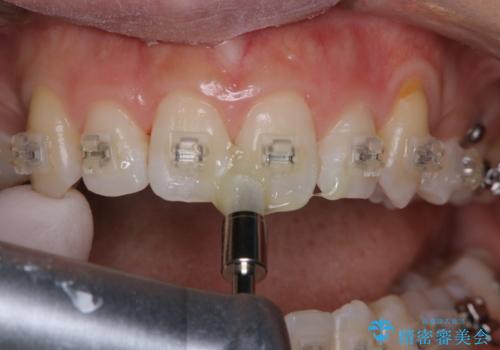

ワイヤー矯正中のPMTC

- ワイヤー矯正中に装置の周りの着色が気になるとのことで来院されました。PMTC30分コースを行いました。

ワイヤー矯正中も、歯の表面に着色(ステイン)が付着することがあります。着色(ステイン)が付着したままだと審美的な問題以外にも、虫歯を発見しずらいことや、細菌が繫殖しやすくなることがあります。クリーニングを行うことで、虫歯や歯周病予防に効果的だったり、もちろん見た目も審美的です。クリーニング後には、汚れが取り除かれ、お口の中がスッキリ・爽快感で気持ちがよくなります。矯正中も定期的にPMTCを行うことが大切です。